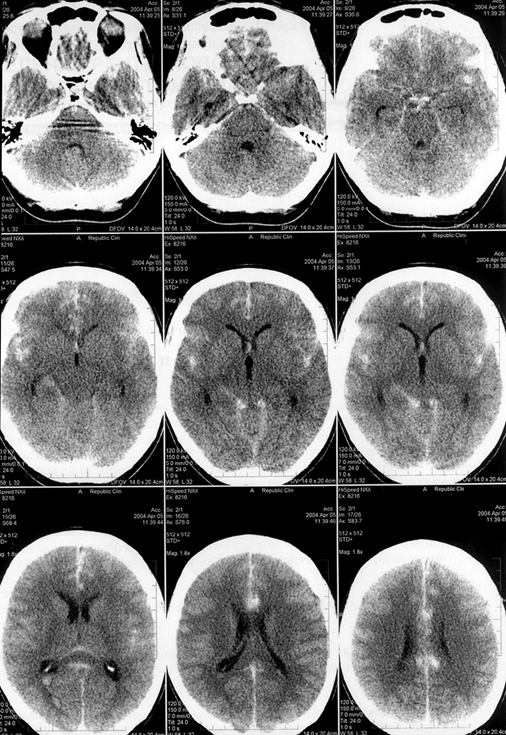

Гематомы задней черепной ямки составляют около 10% всех внутримозговых гематом. Чаще всего они расположены в мозжечке, реже — в стволе головного мозга, где их излюбленной локализацией бывает мост (рис. 12.2).

Кровоизлияния в медиальные отделы больших полушарий мозга, а также гематомы задней черепной ямки приблизительно в 30% случаев сопровождаются прорывом крови в желудочковую систему.

Объем внутримозговых гематом при геморрагическом инсульте может варьировать в очень широких пределах — от нескольких миллилитров до 100 мл и более (см. рис. 12.1, 12.2). Существуют различные способы определения объема гематомы. Наиболее простой из них — способ расчета объема по данным КТ с использованием следующей формулы: максимальная высота × максимальная длина × максимальная ширина : 2. Распределение гематом по объему весьма условно. Принято деление на небольшие (до 20–30 мл), средние (до 50–60 мл) и большие (>50–60 мл) гематомы. Небольшие, средние и большие гематомы встречаются приблизительно с одинаковой частотой.

Рис. 12.2. Внутримозговая гематома червя и обоих полушарий мозжечка (компьютерная томограмма)